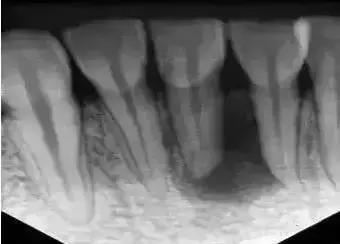

1、术前拍摄X线片:在根管治疗过程中,在根管治疗术前拍X线片,可以帮助诊断,了解髓室的位置和根管数目及形态,测量根管工作长度。

3、确定根管工作长度:应用平行投照X线方法、根管长度测量仪确定根管度,最好插针拍X片。

6、根管充填:封闭整个根管系统、堵塞主根管和侧副根管出口、防止微生物和液体的渗漏。无论是侧方加压法还是垂直加压法,应做到根管充填致密,根管充填后X线片上无根管腔隙,也不能超出根尖孔。

8、完成牙体修复:X线片显示根管充填完好,行暂时或永久牙体修复,带上牙冠,保护患牙,至此根管治疗完成。